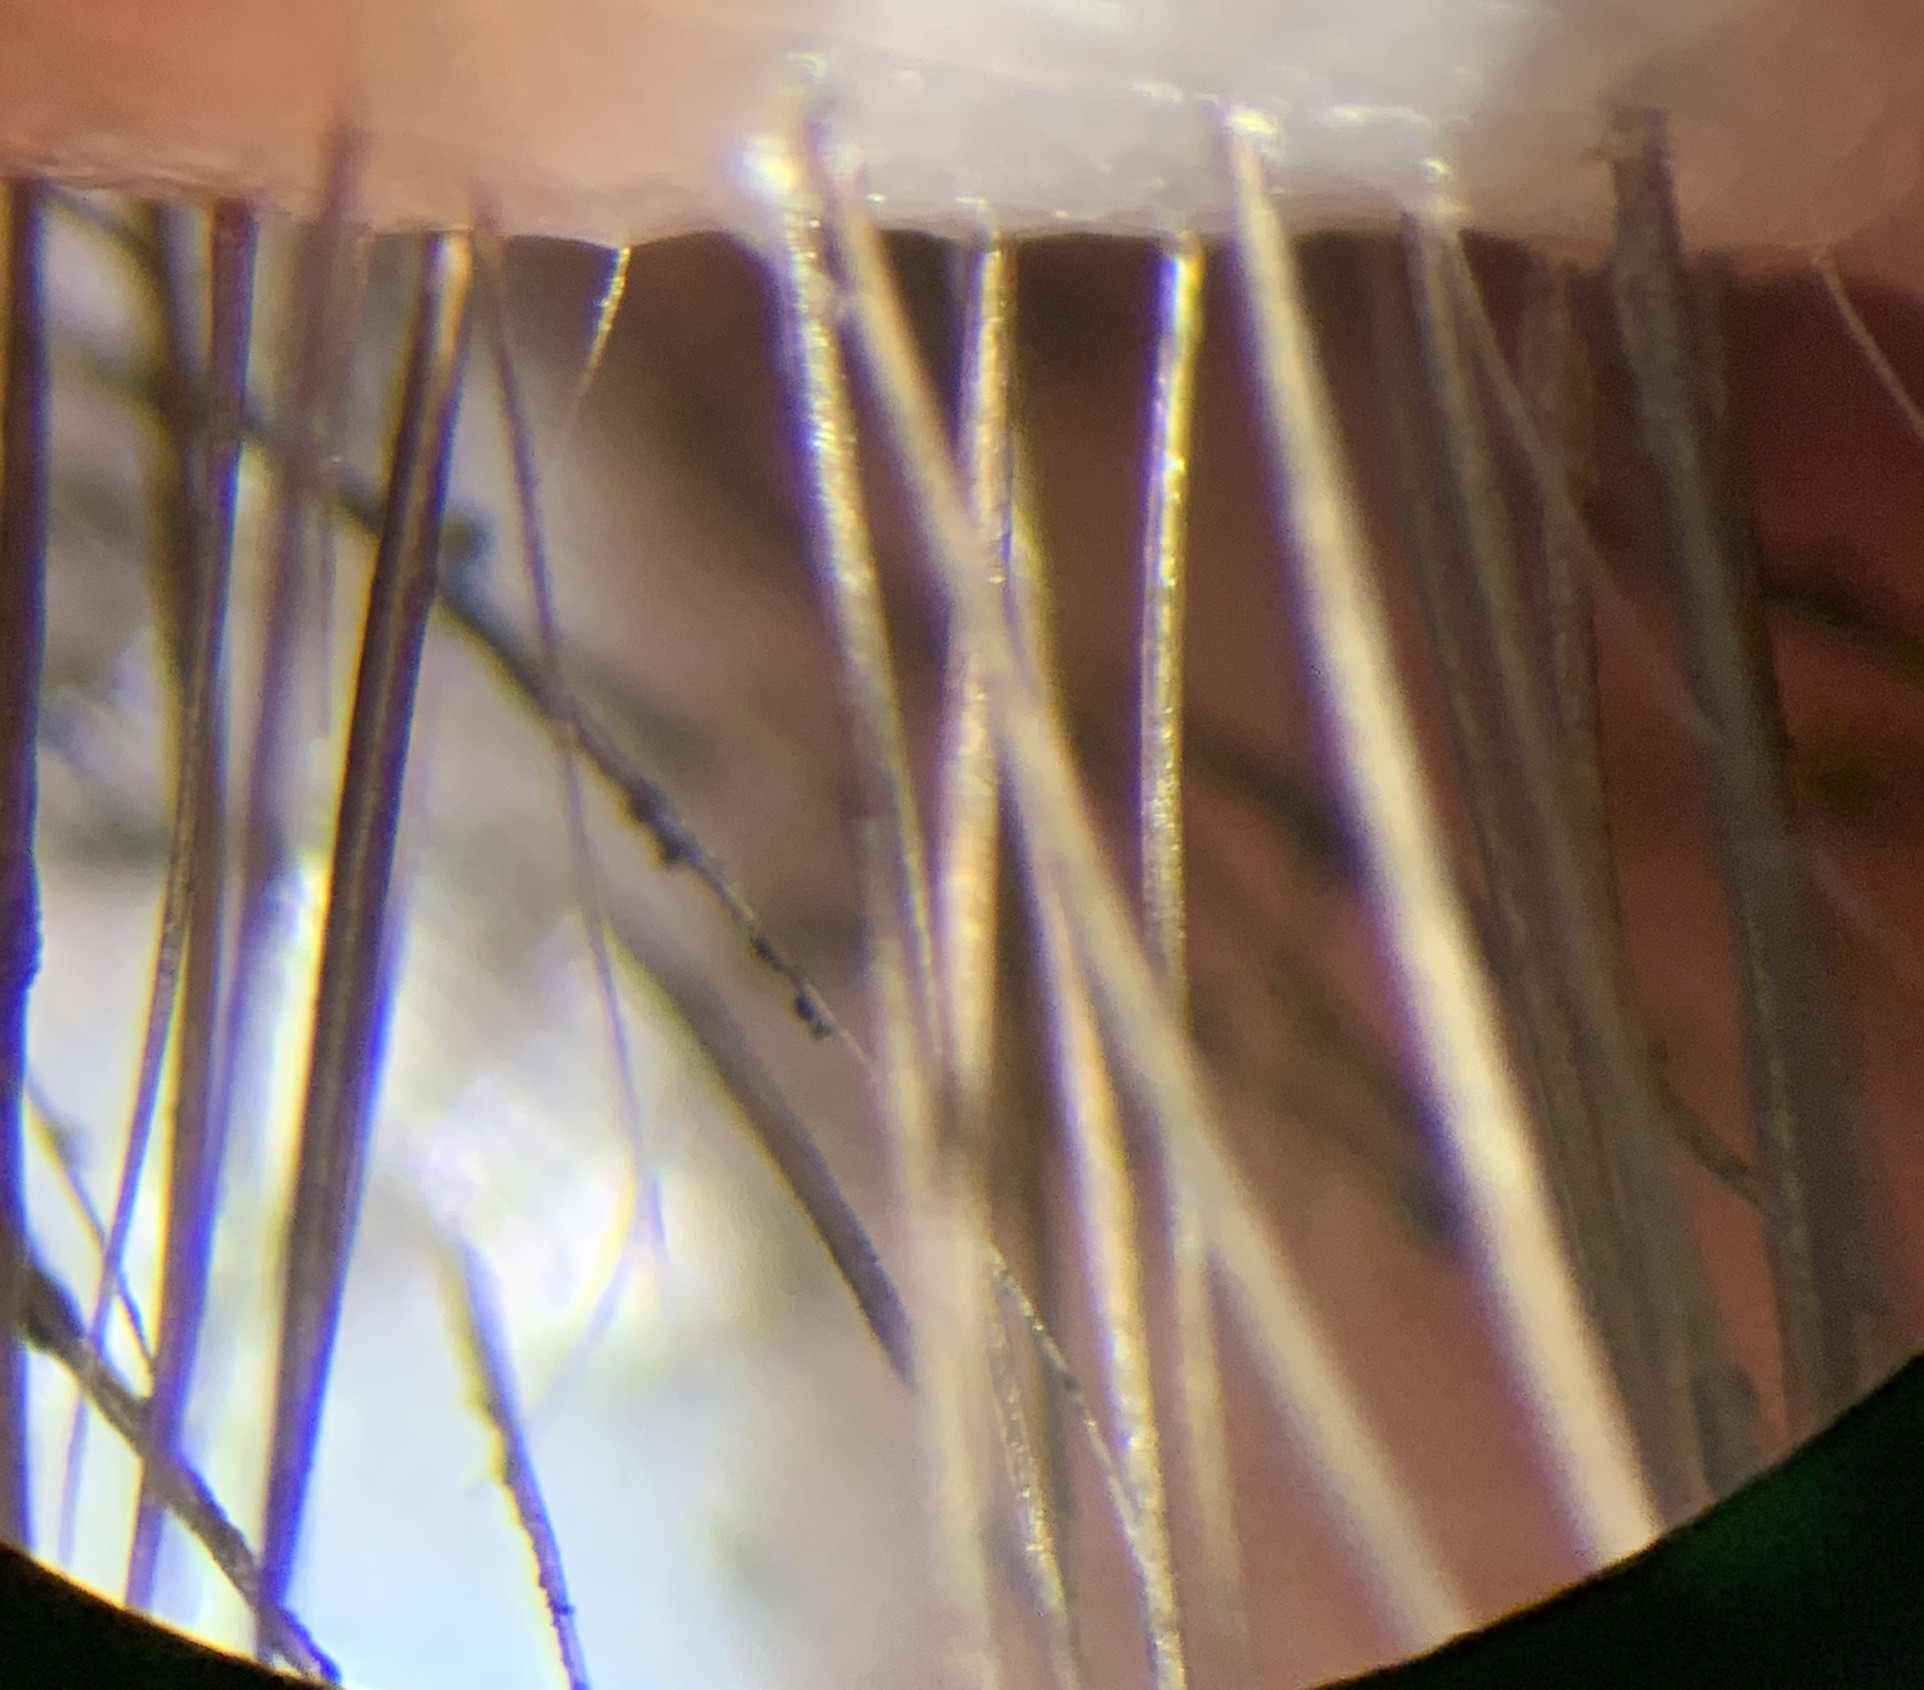

Bio-microscope shows Meibomian glands under high magnification show capping/abnormal secretions indicating specific holistic reatment is requred. 6. Antares (Hanson Medical) measures speed of tear film breaking up. Pointing to targeted treatrment if required, |